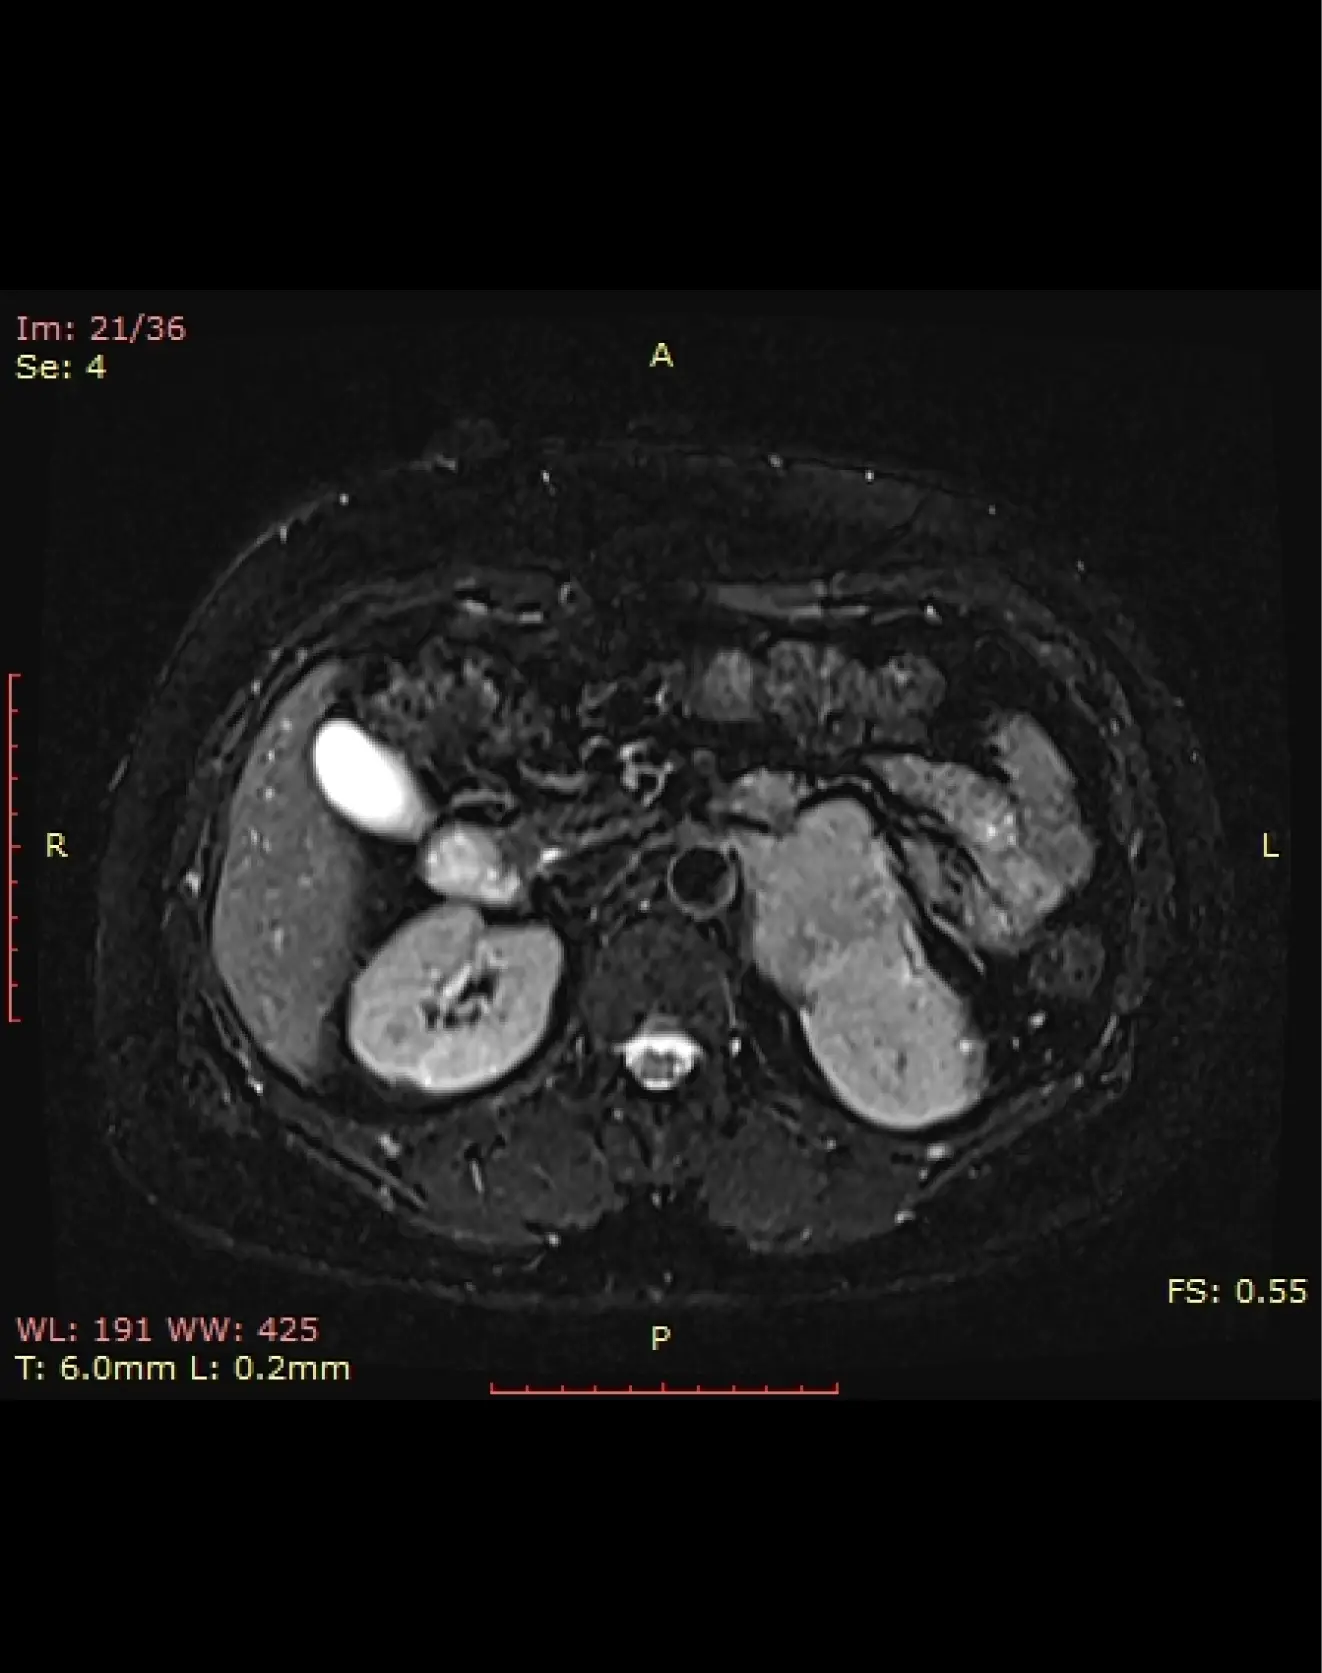

МРТ энтерография (тонкого кишечника с контрастом)

МРТ энтерография – это МРТ тонкого кишечника.Для чего: помогает выявить воспаления, полипы, опухоли и другие патологии кишечника.